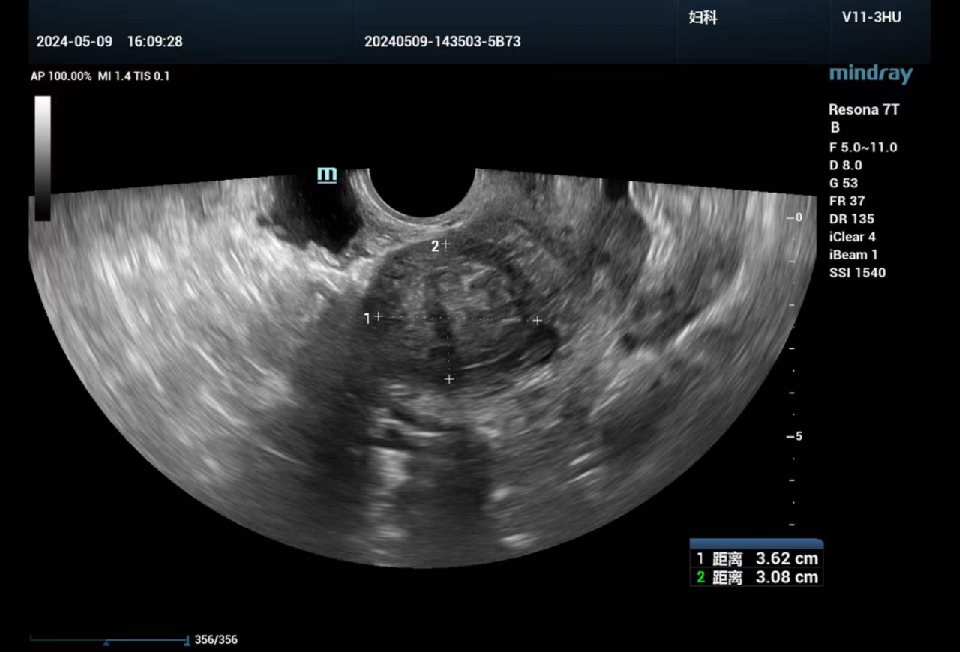

女性,51岁

发现子宫肌瘤2月余。现病史:平素月经规则,7/30天,量中,末次月经2024-4-17,近2年月经周期缩短为23天,月经量较前增多;

妇科超声提示子宫内膜厚0.8cm,子宫前壁探及两枚低回声团块,较大约6.6cm×5.6cm,与内膜相贴,内部回声不均。后突然出现阴道大量出血,急诊就诊霍邱县人民医院血红蛋白89g/L,急诊行分段诊刮术,术后病理:(宫颈管)黏膜慢性炎,(子宫内膜)增生期内膜腺体,部分腺体单纯性增生过长,间质较致密

经腹超声和经阴道超声检查